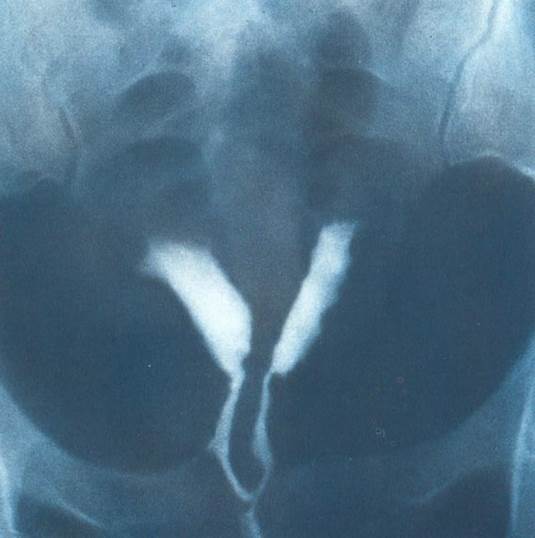

Ваш диагноз при ГСГ: //

pic11.jpg //

Окклюзия маточных труб //

Миома матки //

+Удвоенная матка //

Выход контраста в малый таз